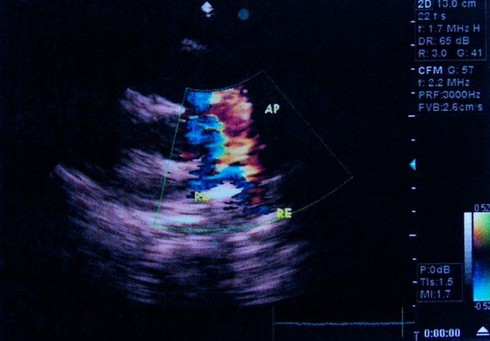

Suy tim:Suy tim xảy ra khi tim không còn khả năng bơm đủ máu đi khắp cơ thể. Hậu quả là máu có thể tích tụ lại trong phổi và khiến người bệnh ho ra dịch màu hồng sủi bọt. |